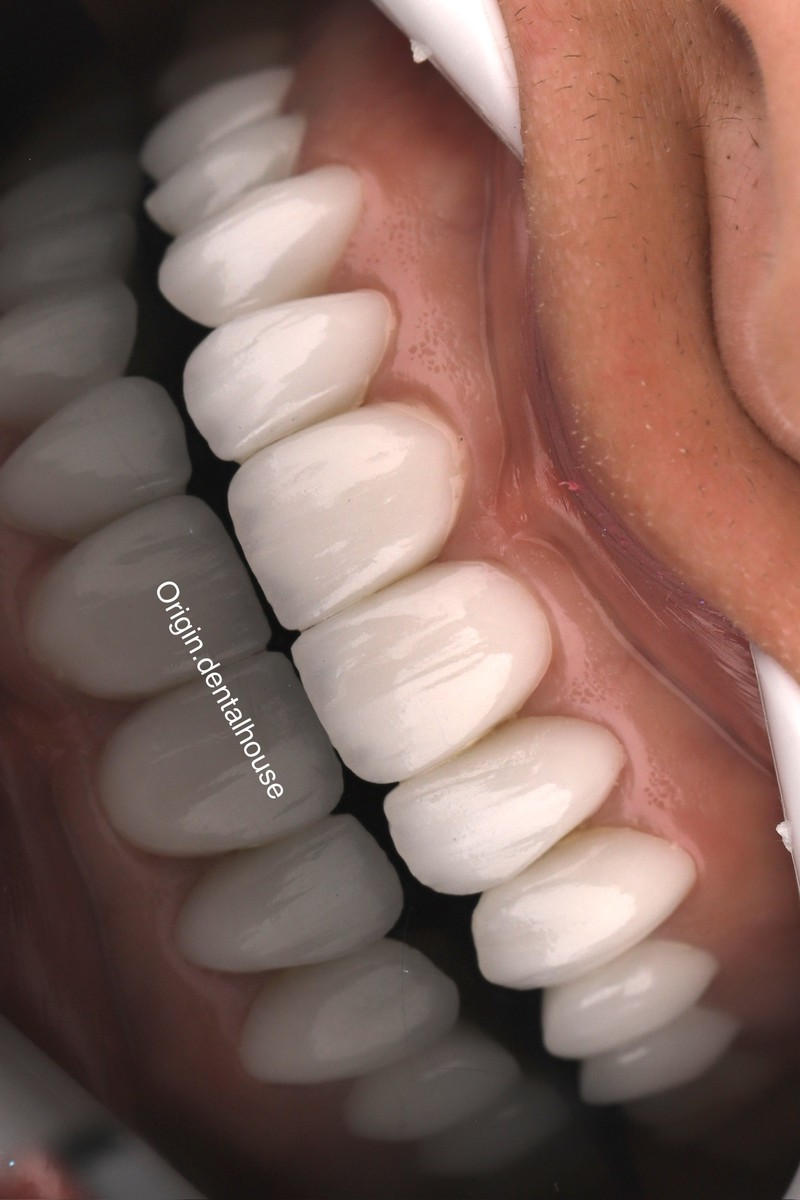

لمینیت سرامیکی دندان(طراحی لبخند) کامپوزیت ونیر دندان (طراحی لبخند) ایمپلنت و کلیه جراحی های تخصصی فک و صورت توسط جراح و متخصص دهان و فک و صورت کلیه خدمات دندانپزشکی به صورت تخصصی با بالاترین کیفیت توسط بهترین دندانپزشکان و در محیط کاملا vip

کلینیک دندانپزشکی دندانپزشکی زیبایی مرکز کامپوزیت دندان مرکز لمینت دندان مرکز ارتودنسی دندان دندانپزشکی کودکان دکتر ارتودنسی کودکان دندانپزشکی اطفال دکتر دندانپزشک متخصص ایمپلنت دندانپزشکی شبانه روزی عصب کشی جراح دندانپزشک جراح دندان عقل جراح لثه جراحی لثه با لیزر متخصص درمان ریشه دندان متخصص لمینت دندان متخصص ارتودنسی ایمپلنت فوری اصلاح طرح لبخند بلیچینگ دندان دندانپزشکی بدون درد کاشت دندان متخصص پروتز دندان ایمپلنت دیجیتال لیفت لثه با لیزر دندانپزشکی با لیزر دکتر دندانساز ایمپلنت اقساطی مشاهده بیشتر